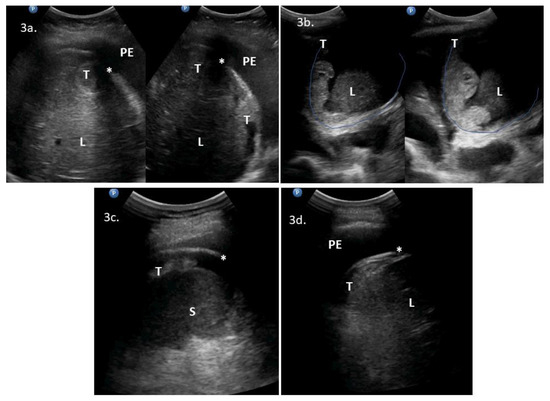

| 3 | 53 | 3 | ascites, massive pelvic involvement, omental involvement | abdominal diaphragm involvement **, pleural diaphragm involvement *, pleural effusions | - | Yes | Yes | YesScore: 6 → 8 Intermediate → High | No | 2c, 2d, 3a, VS2 | PDS, mucinous G3. R = microscopic |

| 4 | 48 | 3 | ascites, carcinomatosis, massive pelvic involvement, omental involvement | abdominal diaphragm involvement **, other *, pleural effusions | ascites, abdominal diaphragm involvement, carcinomatosis, massive pelvic involvement, other *, omental involvement, pleural effusions | Yes | Yes | YesScore: 7 → 9 Intermediate → High | No | 3b, 4c, 4d, VS3 | PDS attempt because of low bowel obstruction symptoms. HGSOC, R > 1 cm. * suspected enlarged cardiophrenic lymph nodes |

| 5 | 79 | 3 | ascites, carcinomatosis, omental involvement | abdominal diaphragm involvement **, pleural effusions, spleen involvement | - | Yes | Yes | Yes Score: 4 → 8 Intermediate → High | No | 3c, 3d, VS4 | DLSK, HGSOC, NACT |